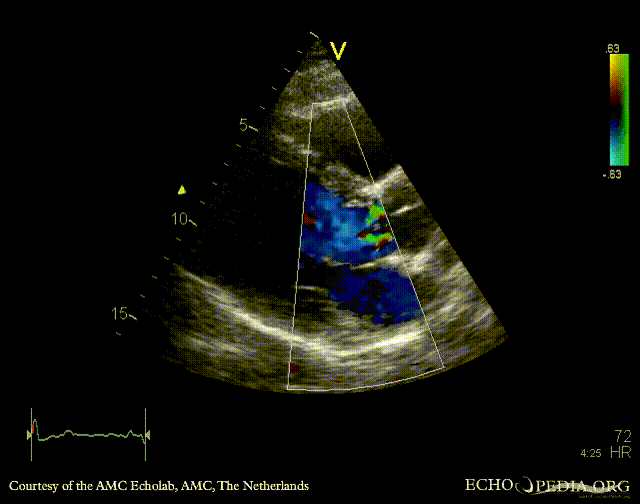

Endocarditis of aortic valve

PLAX: Color Doppler, moderate aortic regurgitation PSAX